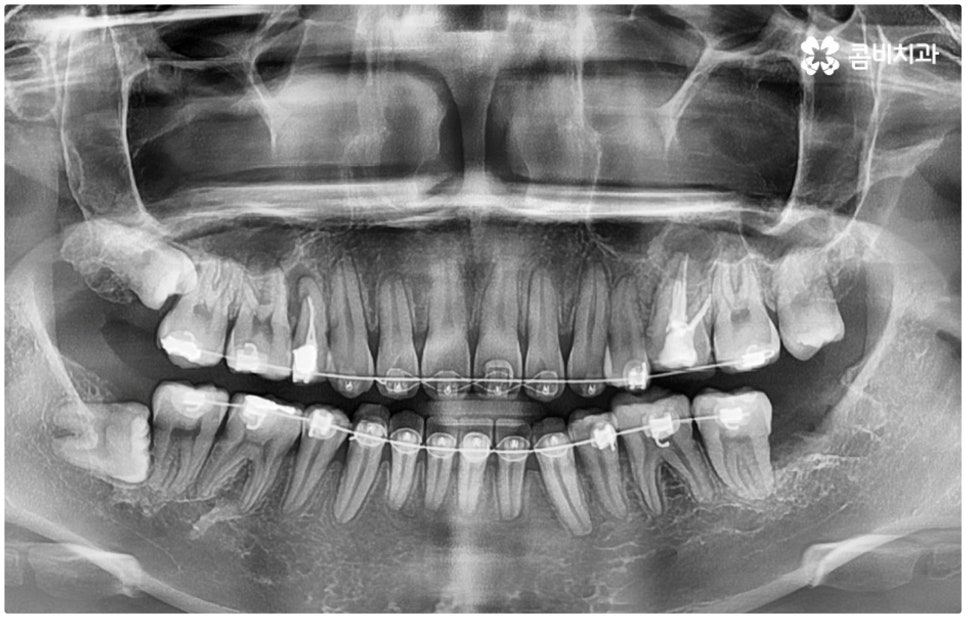

이와 같이 환자분들마다 상황에 맞게 사랑니 발치 시기를 결정하게 되는데 예를 들어 교정을 하는 분들이라면 사랑니를 언제 빼는 것이 맞을까요? 이 역시 검진을 꼼꼼하게 해 본 후에 결과에 따라 달라지게 될 텐데, 만약 아직 사랑니로 인해 충치와 같은 문제가 발생하지 않았고 부정교합 등에 영향을 주고 있지 않다면 교정을 하는 중간 혹은 교정이 끝난 다음 유지 장치를 하면서 적절한 시기에 발치해 주면 될 것이고 구강 질환이 생긴 상태라면 이를 먼저 치료한 다음 원인이 되는 사랑니를 발치한 후 차근차근 교정 치료를 진행하는 것이 좋을 거예요

이때 치과교정과 전문의 자격증과 통합치의학과 전문의 자격증을 동시에 갖추고 있으면서 경력 또한 풍부하신 담당의 선생님께 치료를 받으신다면 중간에 치과를 옮기실 필요 없이 필요한 처치를 제 때 받게되어 보다 편안하게 진료를 보실 수 있어요. 또한 발치를 할 때 무통 마취기 아이젝을 이용하는 매복사랑니발치치과 라면 환자분들의 불편과 통증을 좀 더 줄여줄 수 있으며 보다 안정적인 진료가 가능하니 이에 대해서도 한 번 체크해 보시길 권유드리고 있습니다.